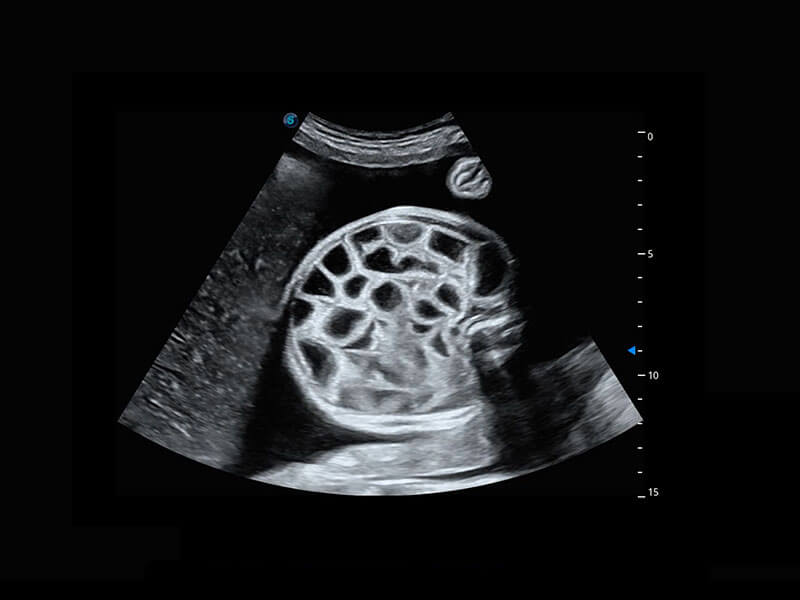

四腔切面

P60搭载一系列胎儿心脏成像技术,实现精细的胎儿心脏评估。